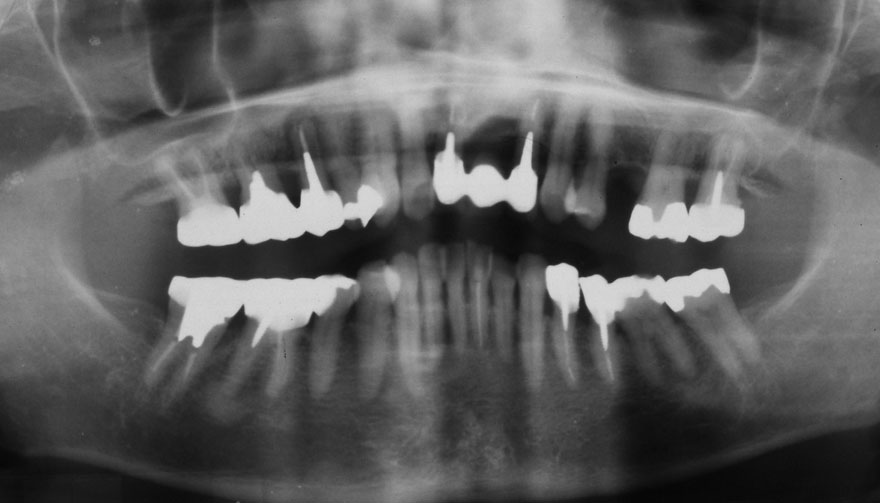

初診時 39歳 女性 平均歯槽骨喪失量:1.82mm

29年後 68歳

平均歯槽骨喪失量:2.21mm

29年間喪失量:-0.39mm

年間喪失速度:-0.013mm

(ケア頻度:5.55ヵ月ごと)